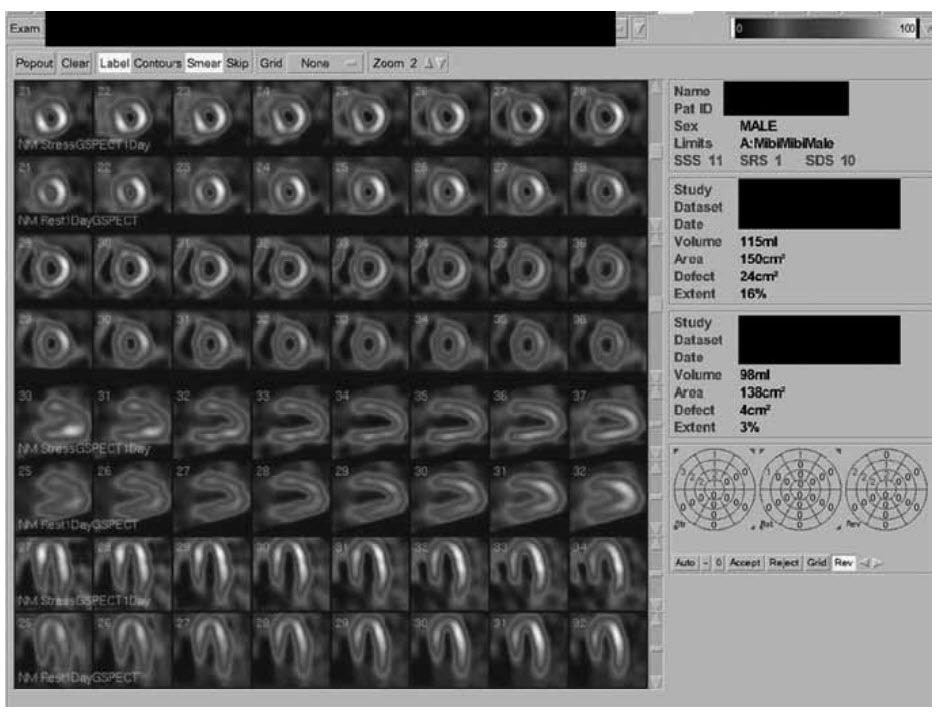

A 63-year-old man presents with a non ST-elevation acute coronary syndrome. His troponin is elevated at 650 ng/L. The ECG is unremarkable. He has a past medical history of familial hypercholesterolemia but is taking no medication. His cholesterol level is 11.3 mmol/L.

He undergoes coronary angiography which reveals triple-vessel disease. A CMR is undertaken to assess myocardial viability. z Video below shows the long-axis cines,

Video below shows the short-axis cines,

and Video below shows the stress perfusion images at the basal (top left), mid (bottom left), and apical (top right) levels.

The late myocardial enhancement images are shown ibelow (top row, left to right: basal, mid, and apical short axis; bottom row, four-chamber view).

Which of the following statements is correct?

A. There is right ventricular infarction

B. The Cx territory is viable

C. The LAD territory is infarcted

D. There is a significant pericardial effusion present

E. The RCA territory is non-viable